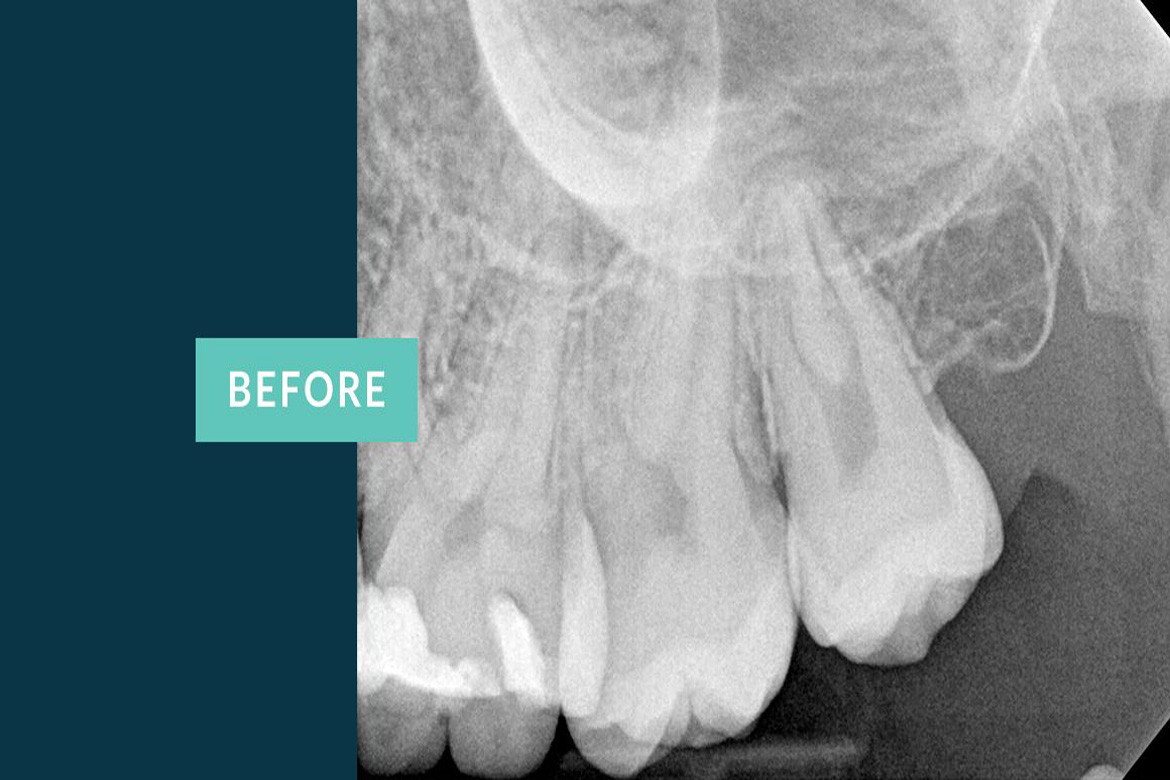

Endodontics is a branch of dentistry associated with the study and treatment of Dental pulp and the tissues neighbouring the tooth Root.

The primary intent of Root canal treatment is to remove the diseased pulp ,clean ,cleanse ,irrigate shape and then fill the canals of the tooth.

The main purpose of root canal treatment is to eradicate Bacteria from the infected tooth irrespective of the number of sittings .If managed well can be done in a single sitting with the similar post operative results as with multiple sittings.